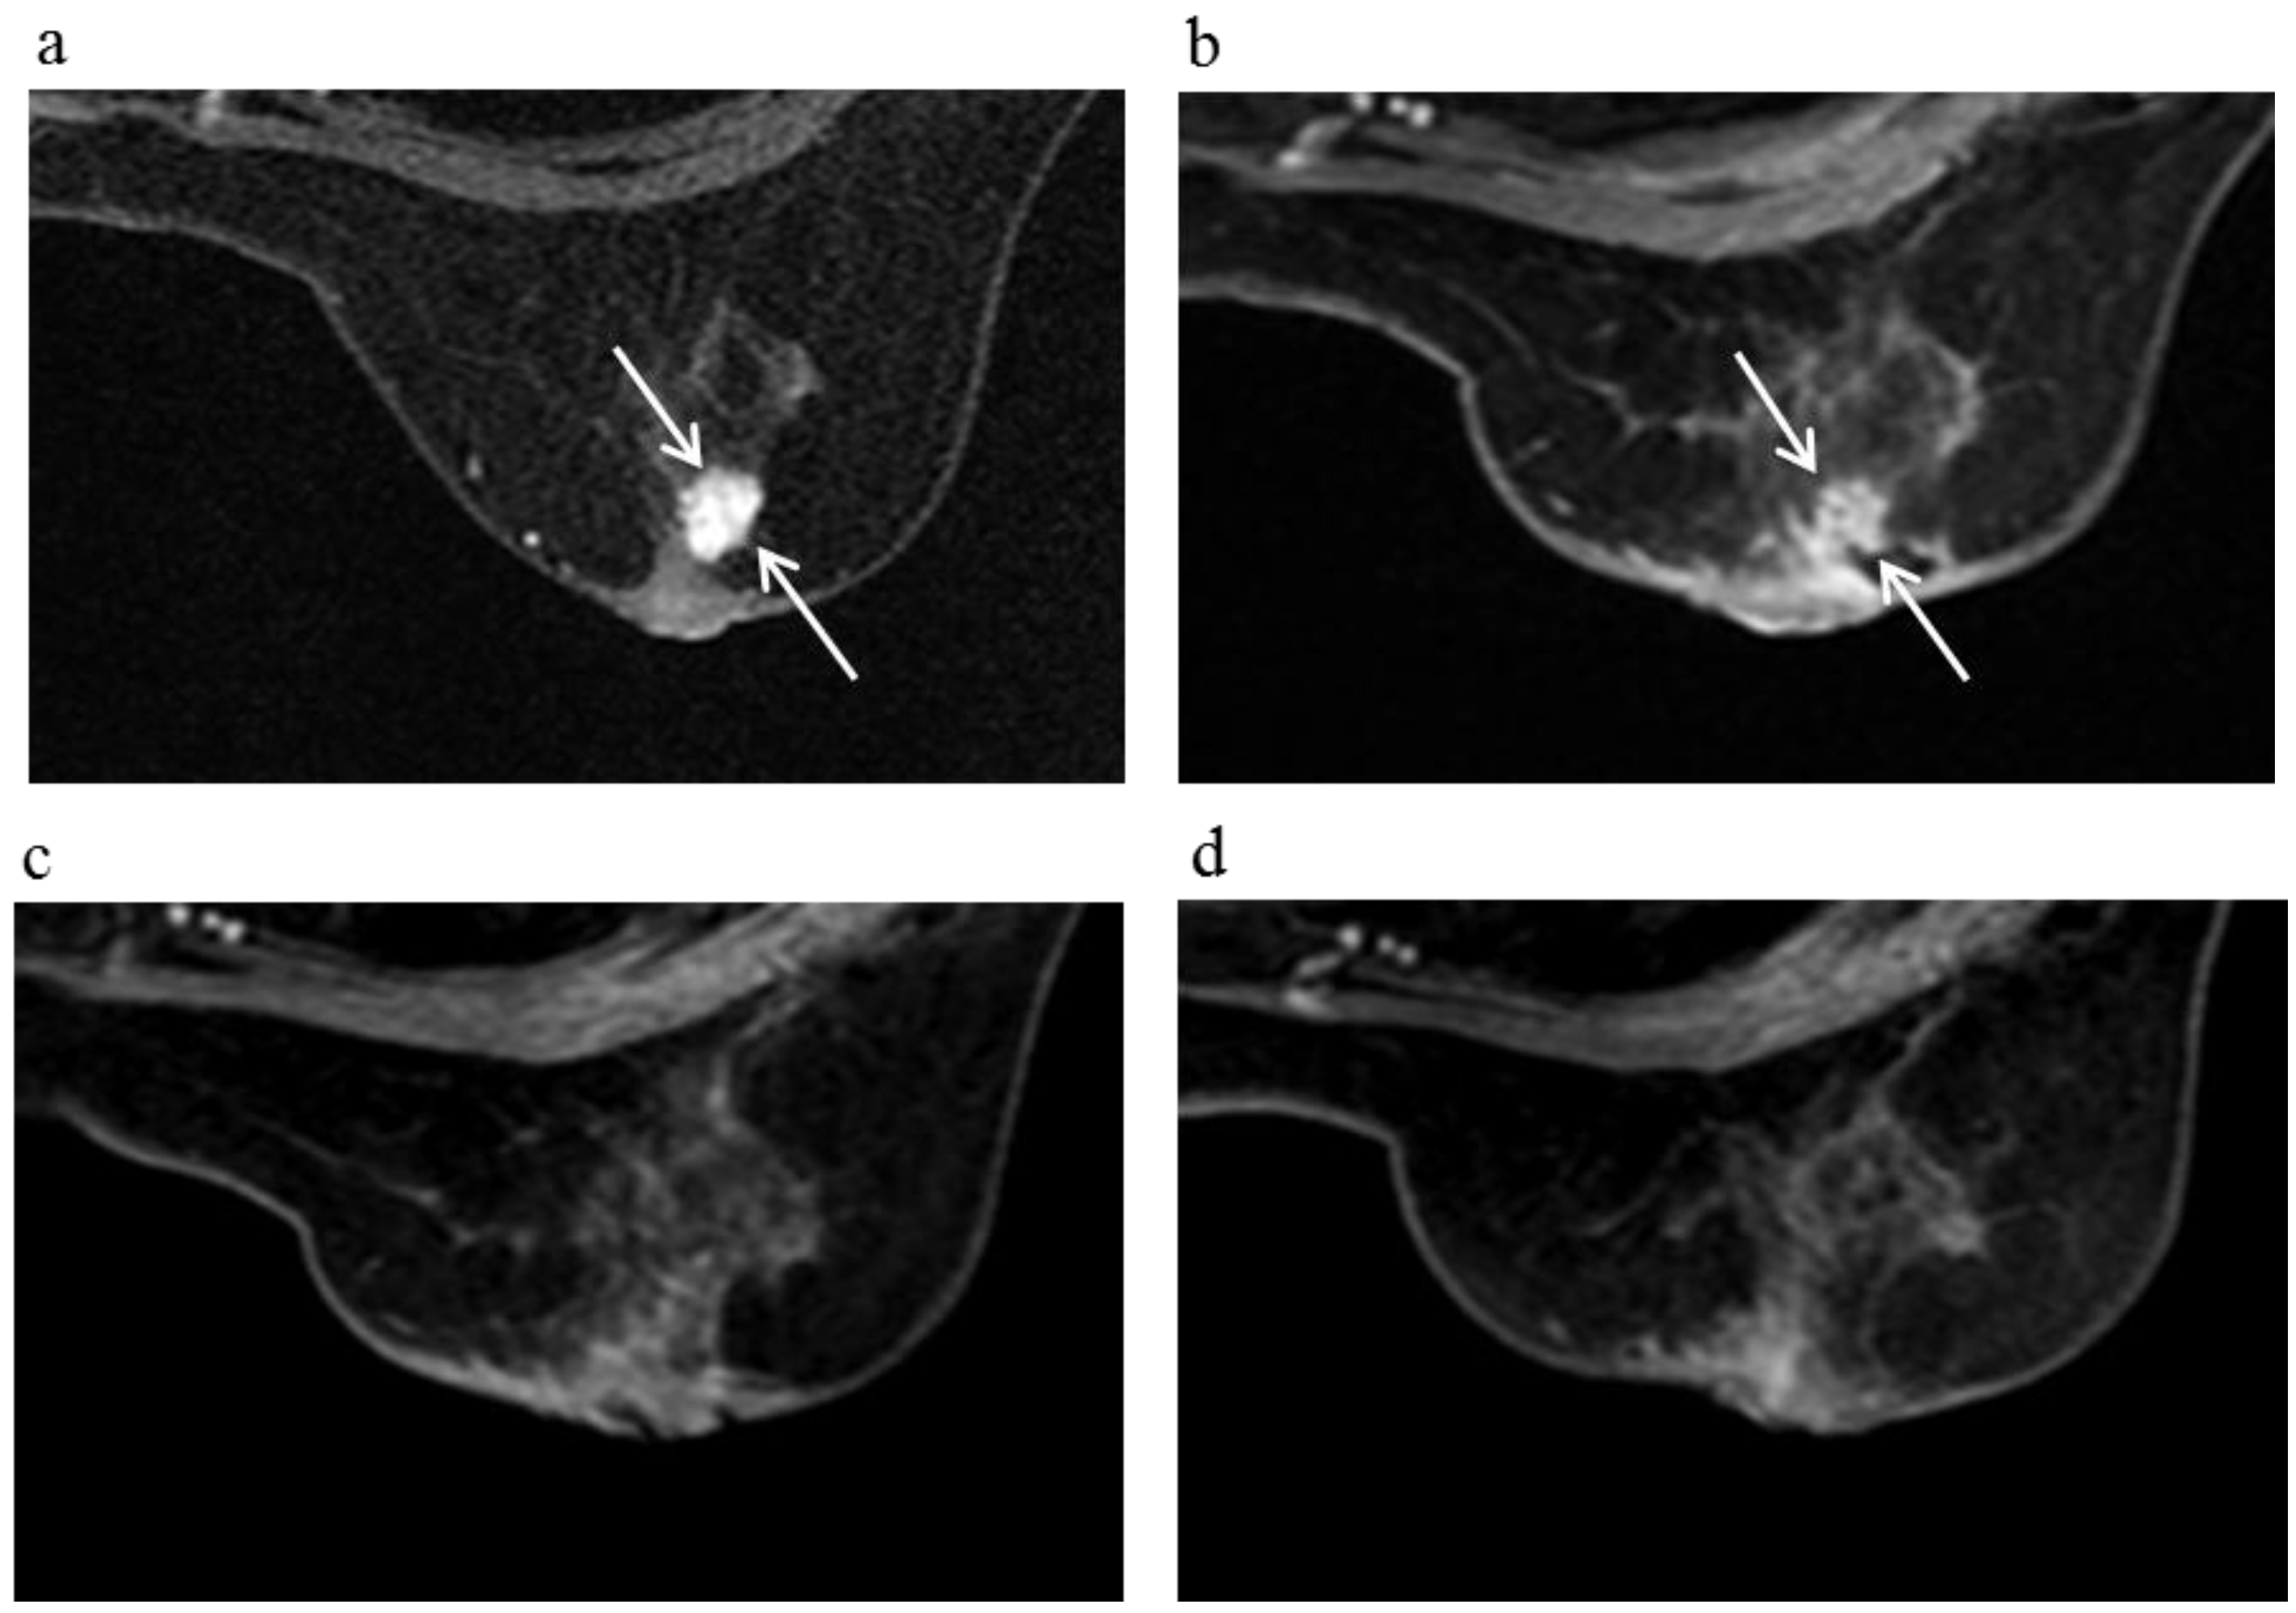

Figure 5.

A 60-year-old female (case 4 in Table 1, Table 2 and Table 3) with right breast cancer (cT1cN0M0). CE breast MRI (a) revealed a breast tumor before KORTUC II therapy, the region of tumor was 18 mm (arrows); After KORTUC II, no recurrence was identified on CE breast MRI ((b): 5 month; (c): 17 month; (d): 29 month; (e): 41 months; (f): 53 months).